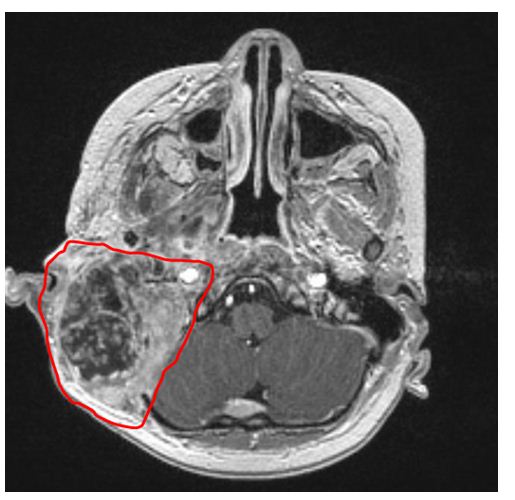

2014年,叮当右耳下隆起一个肿块,检查结果提示恶性肿瘤。在首次切除术后三个月肿瘤复发并迅速增大。在被多家医院告知恶性肿瘤较大无法手术之后,叮当的父母于2016年7月带着叮当首次来到港大深圳医院就诊。港大深圳医院头颈外科、神经外科、儿童肿瘤科等多学科讨论(MDT)后认为,鉴于患儿小,肿瘤大,右侧咽喉旁、颅底的肿块直径达7厘米,病理诊断为恶性程度极高的肉瘤,根据国际循证医学证据,应当先化疗和放疗,等肿瘤缩小后再进行手术切除。2017年2月中旬,叮当接受了“右侧咽旁及中颅窝底肿瘤切除”术。然而,距第二次手术不到一年时间,肿瘤又在叮当的右耳后方复发,有拳头大小,肿瘤溃烂,感染严重,持续高烧不退,命悬一线。在儿童肿瘤专科团队长达2个月多种抗生素联合抗感染及伤口创面处理后,患儿的病情才暂时稳定了下来。

在叮当父母的请求下,港大深圳医院再次组织了MDT:若要将肿瘤切除干净,需要切除被肿瘤侵犯的颈内动脉和椎动脉,随之带来的风险是——右侧大脑供血不足,导致中风、脑梗,最终造成患儿死亡。只有先进行脑血管“搭桥”,移植一根新的血管为叮当的右侧大脑提供供血,然后再将肿瘤及其包裹的血管一并切除。这意味着,叮当的手术要分两次进行:先做脑血管搭桥;再做颅底肿瘤切除。这两个都是大手术,风险大、难度大,对医生技术要求高。